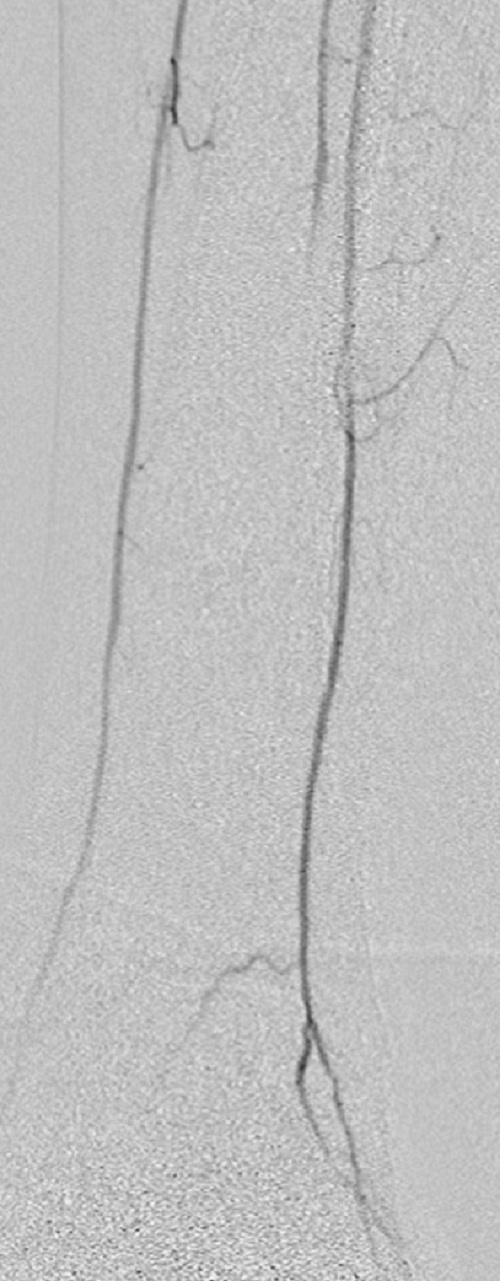

Key to images:

Top panel: Pre-intervention run-off angiogram of the left lower extremity showing, from left to right, irregular left common femoral artery (LCFA) arrowed on the 1st image, absent left superfical femoral artery (LSFA) or any bypass conduit on the 2nd image, sketchy descending collaterals from the left deep femoral (LDFA) that reconstitute a faint shadow of the left popliteal artery, arrowed on the 3rd image. The last 2 images faintly show three-vessel run-off below the left knee. The anterior tibial artery is most opacified, followed by the posterior tibial artery; the peroneal artery peeps through the upper edge of the last image. Note how weakly visible these vessels are due to the poor inflow from above.

When blood flow into or out of a bypass fails, it thromboses and its salvage includes gaining access into it and removing the clot in addition to determining the reason for its failure. Such clot removal may be mechanical, as is frequently the case in acute graft failure, or through thrombolysis, as is the case in later failures. The above images illustrate the later scenario in which the patient presented about 1 year after a left femoropopliteal bypass was fashioned for them. I crossed into the lumen of the bypass conduit from a right common femoral arterial puncture and advanced an infusion cather into it for overnight continuous alteplace infusion following a bolus dose. (I favor 5 to 10 mg of alteplace bolus, followed by continuos infusion at 0.5 mg per hour, in company with fixed unfractionated heparin infusion at 500 units to 600 units per hour after a bolus dose of 3000 units to 5000 units). In this case the bypass proved to be a vein conduit connecting the left common femoral artery, proximally, to the mid popliteal artery, distally, without intimal hyperplasia. The cause of the failure was diminished inflow due to left iliac disease.The final runoff images reveal a three-vessel tibial domain continuous with a near-normal plantar arch.